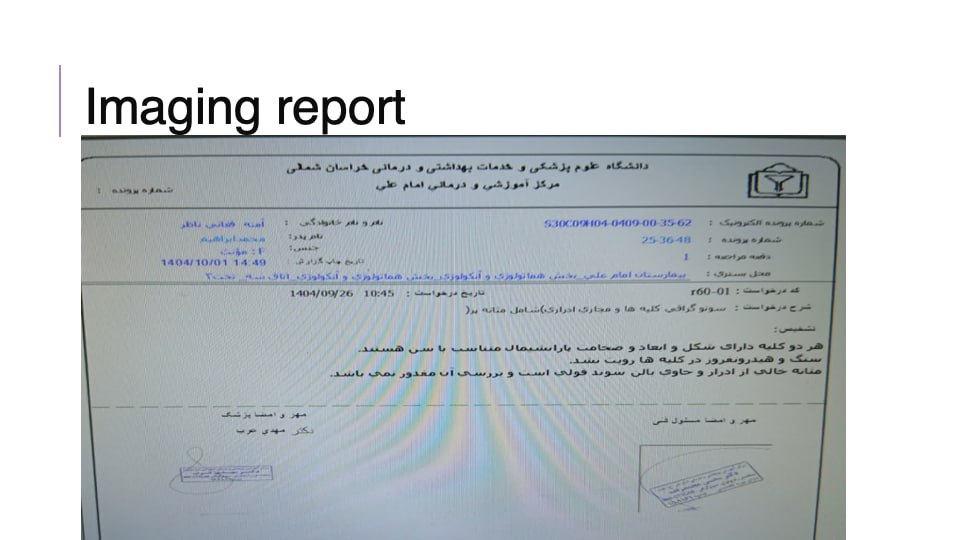

(تصویر مربوط به این مراجعه نیست) Other:

(تصویر مربوط به این مراجعه نیست) Other:

(تصویر مربوط به این مراجعه نیست) Other:

(تصویر مربوط به این مراجعه نیست) Other:

(تصویر مربوط به این مراجعه نیست) Other:

(تصویر مربوط به این مراجعه نیست) Other:

(تصویر مربوط به این مراجعه نیست) Other:

(تصویر مربوط به این مراجعه نیست) Other:

(تصویر مربوط به این مراجعه نیست) Other:

(تصویر مربوط به این مراجعه نیست) Other:

(تصویر مربوط به این مراجعه نیست) Other:

(تصویر مربوط به این مراجعه نیست) Other:

(تصویر مربوط به این مراجعه نیست) Other:

(تصویر مربوط به این مراجعه نیست) Other:

(تصویر مربوط به این مراجعه نیست) Other:

(تصویر مربوط به این مراجعه نیست) Other:

(تصویر مربوط به این مراجعه نیست) Other:

(تصویر مربوط به این مراجعه نیست) Other:

(تصویر مربوط به این مراجعه نیست) Other:

(تصویر مربوط به این مراجعه نیست) Other:

(تصویر مربوط به این مراجعه نیست) Other:

(تصویر مربوط به این مراجعه نیست) Other:

(تصویر مربوط به این مراجعه نیست) Other:

(تصویر مربوط به این مراجعه نیست) Other:

(تصویر مربوط به این مراجعه نیست) Other:

(تصویر مربوط به این مراجعه نیست) Other:

(تصویر مربوط به این مراجعه نیست) Other:

(تصویر مربوط به این مراجعه نیست) Other:

(تصویر مربوط به این مراجعه نیست) Other:

(تصویر مربوط به این مراجعه نیست) Other:

(تصویر مربوط به این مراجعه نیست) Other:

(تصویر مربوط به این مراجعه نیست) Other:

(تصویر مربوط به این مراجعه نیست) Other:

(تصویر مربوط به این مراجعه نیست) Other:

(تصویر مربوط به این مراجعه نیست) Other:

(تصویر مربوط به این مراجعه نیست) Other:

(تصویر مربوط به این مراجعه نیست) Other:

(تصویر مربوط به این مراجعه نیست) Other:

(تصویر مربوط به این مراجعه نیست) Other:

(تصویر مربوط به این مراجعه نیست) Other:

(تصویر مربوط به این مراجعه نیست) Other:

(تصویر مربوط به این مراجعه نیست) Other:

(تصویر مربوط به این مراجعه نیست) Other:

(تصویر مربوط به این مراجعه نیست) Other:

(تصویر مربوط به این مراجعه نیست) Other:

(تصویر مربوط به این مراجعه نیست) Other:

(تصویر مربوط به این مراجعه نیست) Other: